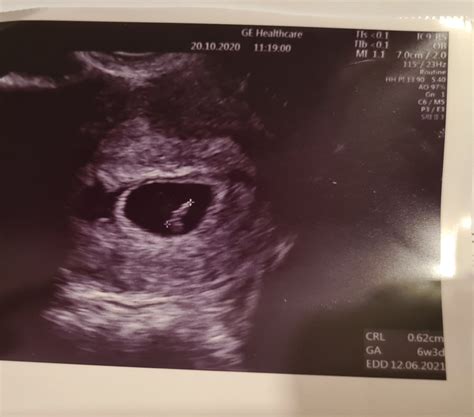

Pri ultrazvukovom vyšetrení v 6. týždni tehotenstva (podľa CRL 8 mm, teda 6+4) bola viditeľná akcia srdiečka. Avšak poznámka "žĺtkový vak nevizualizovaný" môže byť znepokojujúca, najmä v prípade predchádzajúceho spontánneho potratu. V takýchto prípadoch je dôležité konzultovať nález s lekárom, ktorý posúdi všetky súvislosti.

Hladina hCG (humánneho choriogonadotropného hormónu), ktorý je kľúčový pre udržanie tehotenstva, by mala pri perspektívnom tehotenstve v krvi stúpať. V 5. týždni gravidity môže byť viditeľný gestačný vak (GS), v 6. týždni gravidity sa vizualizuje žĺtkový vak (YS) a embryonálny pól (embryo, fetálny pól), pričom koncom 6. týždňa je už možná aj akcia srdca. Ak sú viditeľné všetky tieto štruktúry (GS, YS, embryo), ďalším krokom je často pozvanie pacientky na I. trimestrálny skríning v 11/0 - 13/6 týždni tehotenstva.